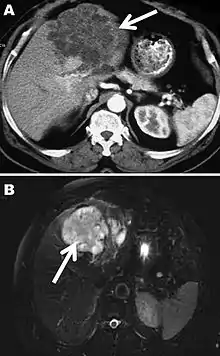

Chez l'humain, les œufs ingérés se transforment en larves qui vont coloniser le foie et former une pseudo-tumeur au bout de plusieurs années. Les larves peuvent exceptionnellement également atteindre d'autres organes comme les poumons ou le cerveau.

L'échinococcose alvéolaire est une maladie grave qui se développe lentement, essentiellement au niveau du foie, sur plus de 15 ans, et de manière asymptomatique. Se traduisant par une hépatomégalie, des douleurs abdominales, un ictère et une fièvre, elle était autrefois souvent confondue avec la cirrhose ou le cancer du foie. La symptomatologie est atypique chez 1/3 environ des patients, avec douleurs abdominales isolées chez 1/3 environ des patients, le dernier tiers présentant une association de symptômes : douleurs abdominales (90 % des cas), hépatomégalie (61 %), altération modérée de l’état général (48 %), ictère, subictère ou prurit (41 %). Il existe une corrélation entre les symptômes et la localisation des lésions[8]. La forme cystique concerne essentiellement le foie et le poumon. La croissance des parasites est longue, sur plusieurs années et le patient est très souvent asymptomatique au début de l'atteinte (ne se plaint d'aucun signe). Les signes apparaissent soit en raison d'une compression d'un organe, soit en raison d'une complication, rupture ou infection. La rupture, tout comme une exérèse mal conduite, peut se compliquer d'une dissémination des kystes à d'autres endroits de l'organisme.